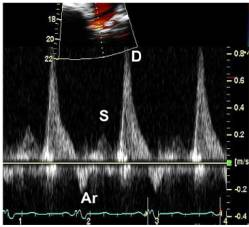

11、肺静脉血流频谱指标

●肺静脉血流频谱:S峰、D峰、S/D比值及Ar峰

●在LVEF小于40%时,与LA顺应性减低与LA平均压增高、增加有关